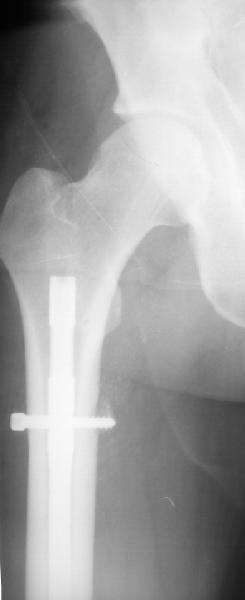

В целом возражений нет, кроме как по предствленному снимку сложно судить о месте введения гвоздя, если через грушевидную ямку или в её районе, то все-таки риск повреждения медиальной огибающей артерии присутствует и кажется Джолдас приводил статистику о последующем развитии ав. некроза головки бедра при антеградном штифтовании через этот порт.